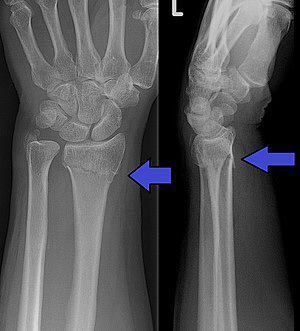

Distal radius fracture